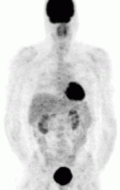

The imaging modalities discussed below are for tumor characterization, confirmation of metastatic disease, and treatment planning - they are not used to discern tumor location or help the surgical team prepare for excision.[82] For most pheochromocytoma patients, functional imaging will follow a CT or MR. If anatomic imaging only demonstrates an adrenal tumor without evidence of disease anywhere else in the body and the metanephrine levels are overtly elevated, functional imaging can be foregone in favor of prompt surgical excision.[77] Over the last decade, there have been five functional techniques used to evaluate the pheochromocytoma patient (1) 18F-fluorodeoxyglucose positron emission tomography (18F-FDG PET), commonly referred to as the PET scan, (2) iodine-123 meta-iodobenzylguanadine (123I-MIBG), (3) 18F-flurodihydroxyphenylalanine (18F-FDOPA),(4) 68Ga-DOTA coupled somatostatin analogs (68Ga-DOTA),(5) 11C-Hydroxy ephedrine(HED-PET). From this point forward, these imaging modalities will be referred to in their abbreviated names found in parentheses.

The first functional imaging technique utilized in pheochromocytoma patients was 123I-MIBG scintigraphy (Image Right). Given the compounds similar structure to the catecholamine norepinephrine (secreted by pheochromocytomas), MIBG was well-suited for uptake by most neuroendocrine tumors.[83] Furthermore, if a patient was found to be positive on an MIBG scan, they were eligible for MIBG treatment, offering additional avenues for those suffering from widespread metastatic disease.[84] However, further investigation revealed that while MIBG excelled with adrenal lesions, it was far less superior in patients with extra-adrenal paragangliomas, particularly with specific genetic variants like succinate dehydrogenase subunit X (SDHx).[72] As the positron emission tomography scans were developed, MIBG has slowly loss its favor for the pheochromocytoma patient.[72]

Of the four above mentioned modalities, 18F-FDG PET is the most common and readily available functional imaging technique at most hospital systems, but the least-specific to neuroendocrine tumors (Image Left). In 2012, over 200 patients participated in a trial that compared the current gold standard of the time (MIBG/CT/MRI) to the novel FDG PET. Compared to its functional counterpart, FDG outperformed MIBG in detecting soft-tissue and bone metastases with a higher specificity in patients with biochemically active tumors.[72]